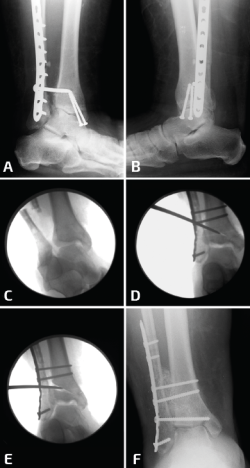

Se puede recurrir a la osteotomía de la tibia para corregir la deformidad en valgo del pilón. Esto se puede realizar mediante una cuña de sustracción interna o una cuña de adición externa de la tibia (Figura 6). En este caso, la consolidación viciosa oblicua del peroné facilitará la osteotomía oblicua del mismo para lograr una buena elongación y en este caso no se utilizaría injerto óseo(11).

Figura 6. En un caso donde el plafón tibial se encuentra en valgo, solo elongar el peroné no será suficiente. Observen el pie plano como resultado del tobillo y el retropié en valgo (A, B). Se realizaron conjuntamente una elongación del peroné, una osteotomía en cuña de cierre con base medial de la tibia y una osteotomía medializadora del calcáneo. Observen una mejoría en la alineación, pero la persistencia de un leve valgo de tobillo (C, D).

Debido a la deformidad en valgo del tobillo y la artritis precoz, se debe realizar una osteotomía simultánea de la tibia para alinear las fuerzas de carga sobre el tobillo, ya que solo con la elongación del peroné no es suficiente. Los tejidos que rodean el peroné podrían necesitar desbridarse elevando el periostio por completo y luego se moviliza el peroné sobre su pedículo distal (Figura 7).

Figura 7. En este caso, además de una deformidad en valgo del plafón, se agrega una pseudoartrosis del peroné con acortamiento del mismo y un ensanchamiento de la sindesmosis. Solo se ve la mitad lateral del plafón impactada en valgo, por lo que una osteotomía en cuña de cierre con base medial de la tibia no es necesaria (A, B). Se desbrida la sindesmosis y se retrae el peroné hacia lateral (C), se elonga y se realiza una osteotomía intraarticular (plafonplastia) del borde lateral de la tibia (descrita por Myerson) (D). La tibia lateral se distrae gradualmente hasta observar la posición neutra del pilón (E); se coloca injerto óseo y se estabiliza la sindesmosis (F).